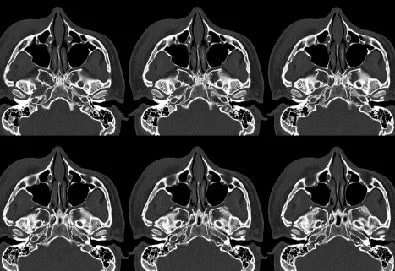

Tomografía de Senos Paranasales

La tomografía de los senos paranasales es un estudio tridimensional que permite evaluar con alta precisión las cavidades aeradas de la cara (senos frontal, maxilar, etmoidal y esfenoidal), incluyendo sus paredes óseas, ostiomeatales y mucosa de revestimiento, facilitando la detección de inflamaciones, obstrucciones, infecciones crónicas, pólipos, alteraciones anatómicas y cambios patológicos, aportando información clave para el diagnóstico y la planificación de tratamientos en especialidades como otorrinolaringología, cirugía endoscópica sinusal y alergología.